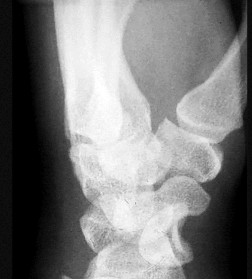

Question 19:

A 35-year-old female sustains a twisting injury to her ankle. Radiographs reveal a transverse fracture of the medial malleolus and a spiral fracture of the proximal third of the fibula (Maisonneuve fracture). For this specific fracture pattern to occur, which of the following ligamentous structures MUST be completely disrupted?

Correct Answer: Syndesmotic ligament complex and interosseous membrane

Explanation:

A Maisonneuve fracture is a pronounced variation of a pronation-external rotation (PER) injury. The mechanism involves external rotation of the talus, which either avulses the medial malleolus or ruptures the deltoid ligament, then disrupts the anterior inferior tibiofibular ligament, tears up the interosseous membrane all the way to the proximal fibula, and exits as a high fibular fracture. Therefore, the syndesmotic complex and the interosseous membrane up to the level of the fracture are intrinsically disrupted.